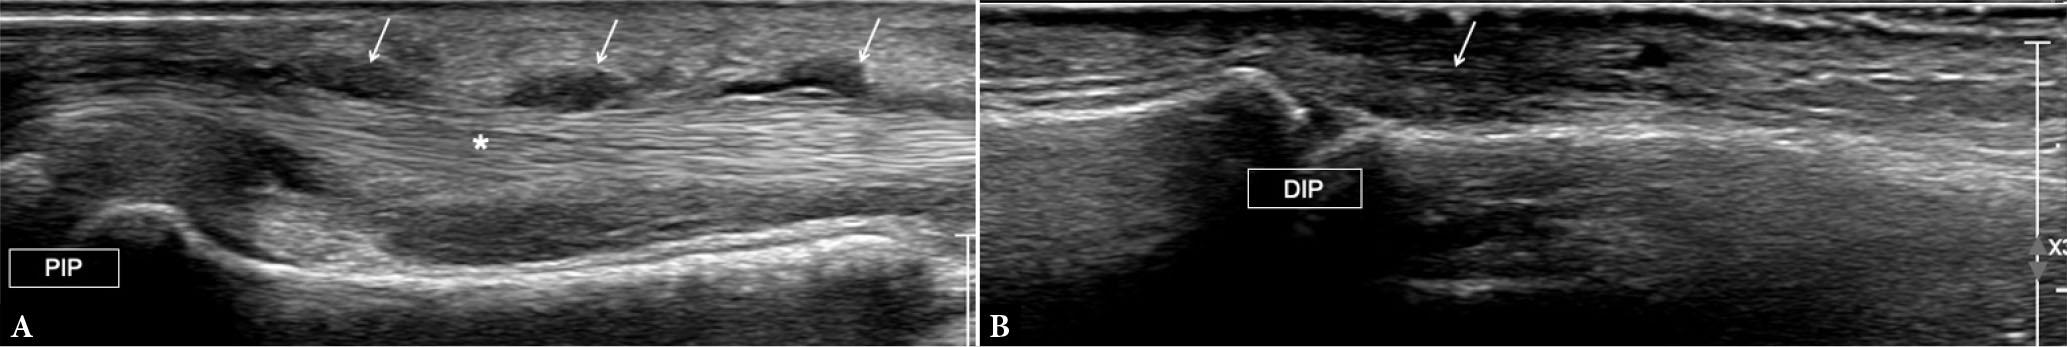

Fig. 17.

Dactylitis. Long-axis US image of flexor tendons (A) and extensor tendon (B) of the fingers of the same patient show tenosynovial proliferation (arrows in A) around flexor tendons (asterisk), representing tenosynovitis. There is thickening of the extensor tendon (arrow in B) at its insertion to the distal phalanx. PIP – proximal interphalangeal joint; DIP – distal interphalangeal joint